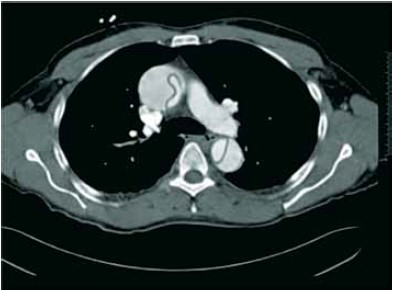

Considere o caso clínico a seguir, para responder à questão.

Paciente de 56 anos, sexo feminino, portadora de hipertensão arterial, com episódio de síncope após realizar esforço evacuatório. Chega ao pronto atendimento após 20 minutos.

Ao exame fisico:

– Rebaixamento do nível de consciência, escala de coma de Glasgow 5.

– Ritmo cardíaco: sopro diastólico aspirativo e em decrescendo.

– Frequência cardiaca: 120 bpm.

– Pressão arterial (MSD): 90 x 54 mmHg.

– MV+ difusos diminuidos em bases.

– Pulso radial à esquerda filiforme menor que à direita.

Após realização das medidas iniciais na sala de emergência, realizou uma tomografia de torax.

Enunciado 3417352-1

O tratamento de escolha neste caso clínico é:

Enunciado 3417351-1

Em relação ao mecanismo fisiopatológico associado a essa doença, o principal fator de risco associado é: